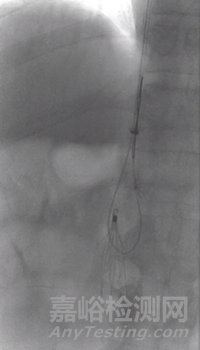

3. 41天濾器回收:

造影示下腔靜脈通暢,濾器形態(tài)居中,下方未見血栓形成。置入10F回收鞘,順利回收